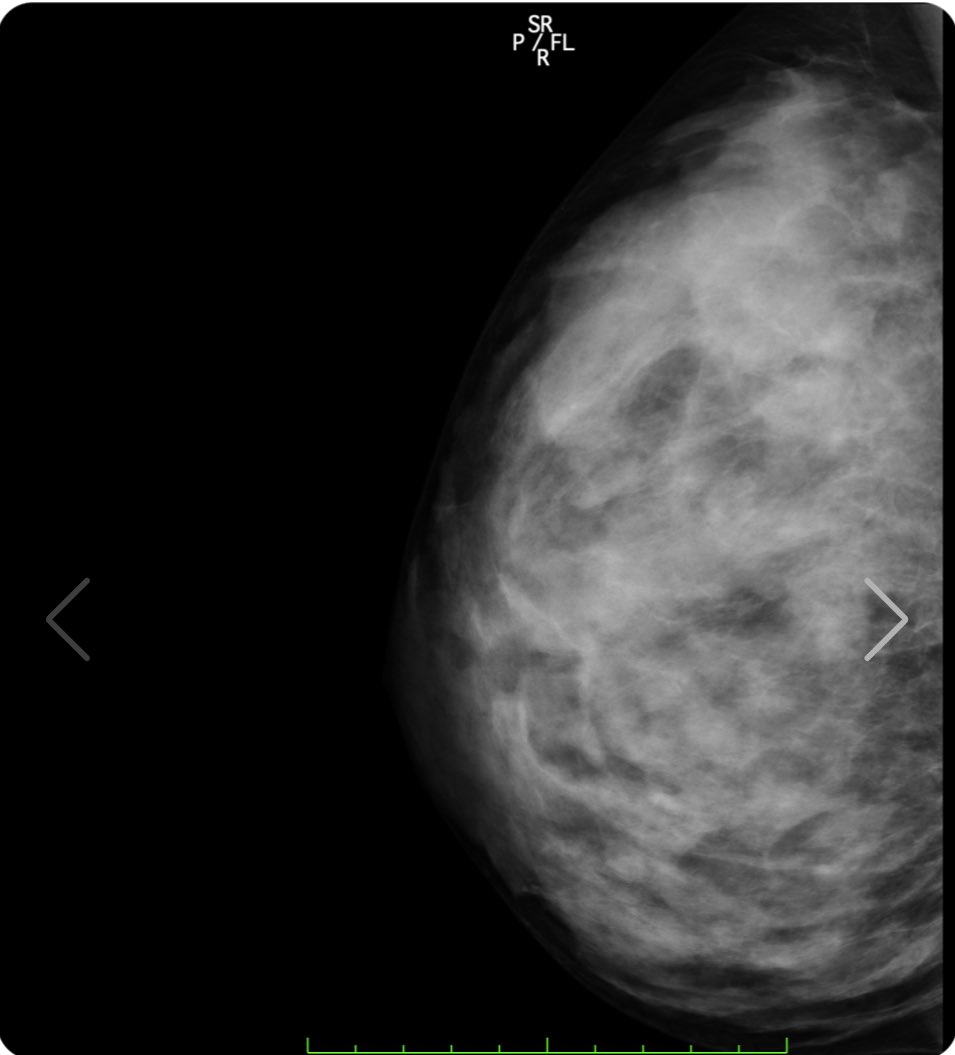

人気爆乳グラドル天木じゅん、スケスケの丸見えオッパイを解禁し偽乳疑惑を払拭するww グラビア天木じゅん 2021年8月21日 7:07 17コメント Tweet ※当サイトはアフィリエイト広告を利用しています 似ている人気記事 バスト約100cm美少女ちとせよしの、紐タイプのハイレグ衣装でえちえちなバニーコスプレに挑戦しほぼ裸の格好にww 長身×巨乳×美脚の現役バニーガール 蜂羽レム、店から黙って拝借したバニーコスを着てノリノリAVデビューwww 名門ミスコン「ミスマガジン」2021~2023の3世代・18名が大集合、個性溢れるビキニ姿を見せてるww ertkな名無し レントゲンでもわかるエロいおっぱい 私の胸部レントゲン!www正面から見た写真の右の胸の黒いのは胃泡だよ安心してね裸を通り越して私の骨と脂肪を見れたあなたには幸運が訪れると信じてます❤️(私の胸は遺伝です)w#1mmでもいいなと思ったらRT #胸部レントゲン #人間ドック pic.twitter.com/OmgFNaRvui— 天木じゅん (@jun_amaki) August 18, 2021 ertkな名無し 医者になればオッパイのレントゲン見放題か・・ ertkな名無し これは本物 小池栄子様♀️♀️♀️#1mmでもいいなと思ったらRT #天木TikTok pic.twitter.com/8vkmhu0LD2— 天木じゅん (@jun_amaki) August 9, 2021 ertkな名無し 綺麗な肺ですね まさにフルヌード 撮影頑張ってきます♥︎#1mmでもいいなと思ったらRT pic.twitter.com/BO6j7hkZqW— 天木じゅん (@jun_amaki) August 10, 2021 9th DVD『じゅんちゃん♡』絶賛予約受付中https://t.co/F94nYpmxMOオフショットだよっっ#1mmでもいいなと思ったらRT pic.twitter.com/76ljB26SHC— 天木じゅん (@jun_amaki) August 15, 2021 天木じゅん 最新作 https://www.dmm.com/mono/dvd/-/detail/=/cid=n_701tsds42550tk/ サンプル再生 こちらの「サンプル再生」でも見れます 天木じゅんの関連記事:アンテナからエロチカ記事へのリンク 天木じゅんが初DVDでIカップの爆乳使ってパイズリwww 枕営業が話題の仮面女子が冠番組でスク水で入浴百合プレイwww 仮面女子天木じゅんのHカップ爆乳使った隠し芸が卑猥すぎwwwwww コメント 通りすがりの紳士:2021/8/21 7:34 アッハイ 通りすがりの紳士:2021/8/21 8:35 おっぱい 通りすがりの紳士:2021/8/21 8:47 問題は乳じゃないんだっていい加減気付けよ。 通りすがりの紳士:2021/8/21 8:50 天木じゅんがどうとかいうわけじゃなくレントゲンなんて何の意味もないぞ シリコンバッグじゃなくて脂肪注入じゃレントゲンでわからんからな 昔はペチャパイだった、ほしのあきが偽乳疑惑かわすためにTVの企画ですでにやってる。 通りすがりの紳士:2021/8/21 10:24 ぶち込みたいわ 通りすがりの紳士:2021/8/21 10:41 俺はずっと信じてたぜ!じゅんちゃんの唯一の存在意義は乳袋なのにそれで嘘つくわけないよ! 通りすがりの紳士:2021/8/21 11:04 >>6 拾い物って言葉知ってる?残念だけど偽乳って周りが認識してしまったらそれはもう偽乳なの 同じカップ数なら柳瀬さきのが至高ですよ? 通りすがりの紳士:2021/8/21 11:21 流石にこれが偽乳と言うのは無理があるよなw 通りすがりの紳士:2021/8/21 11:26 ぶち込みたいわ、 通りすがりの紳士:2021/8/21 11:33 >>8 お前の思考に無理がある() 通りすがりの紳士:2021/8/21 16:36 最近は脂肪吸引したもの以外にも、ヒアルロン酸をうつ豊胸もあります。 効果の時間は脂肪吸引より短いですが、メスを使わないので安全ですし 写真集を出す前とかに少しボリュームをアップするのに効果があります。 通りすがりの紳士:2021/8/21 18:43 顔がねぇ 通りすがりの紳士:2021/8/21 19:08 ※12 キモメンのお前が言える顔じゃねえだろ 通りすがりの紳士:2021/8/21 19:56 ていうか今回はアイドル学園公式サイトではサンプル画像無いのね…ひそかに楽しみにしてたのに… 通りすがりの紳士:2021/8/21 20:19 高濃度乳腺 通りすがりの紳士:2021/8/21 21:16 ※13 一般人とアイドル比べてどうすんのw 通りすがりの紳士:2021/8/22 13:27 偽乳じゃない証明ならレントゲンじゃなくブラックライト照らせば一発でわかるのにw 静止画だと解りづらいが動画だと顔が不自然なのが解る。 コメント Δ 日本語が含まれない投稿は無視されますのでご注意ください。(スパム対策)

高濃度乳腺